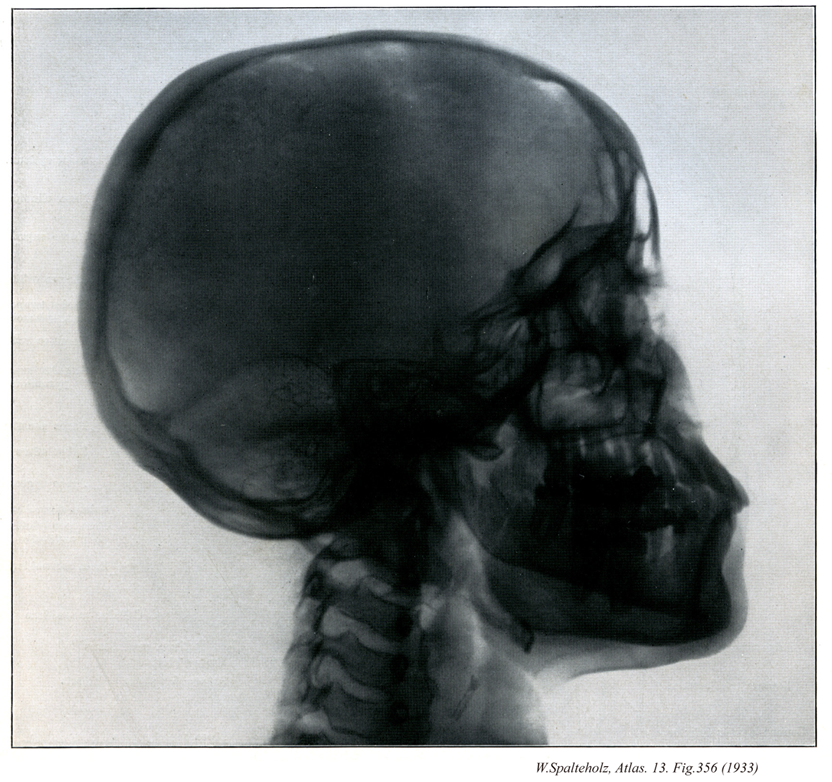

【Bones of cranium; Skull bones

頭蓋骨;ズガイコツ

Ossa cranii】

→(頭蓋は15種23個の骨、すなわち10種16個の頭蓋骨および5種7個の顔面骨とにより形成されている。頭蓋骨は中枢神経系および感覚器に接する部分を形成する骨格で後頭骨(1個)、蝶形骨(1個)、側頭骨(1対2個)、頭頂骨(1対2個)、前頭骨(1個)、篩骨(1個)、下鼻甲介(1対2個)、涙骨(1対2個)、鼻骨(1対2個)、及び鋤骨(1個)である。頭蓋を構成する骨の分類には諸学者による見解の相違があり、後頭骨、蝶形骨、側頭骨、頭頂骨、前頭骨の5種7個を脳頭蓋とし、他の10種16個を顔面骨とする意見もある。)